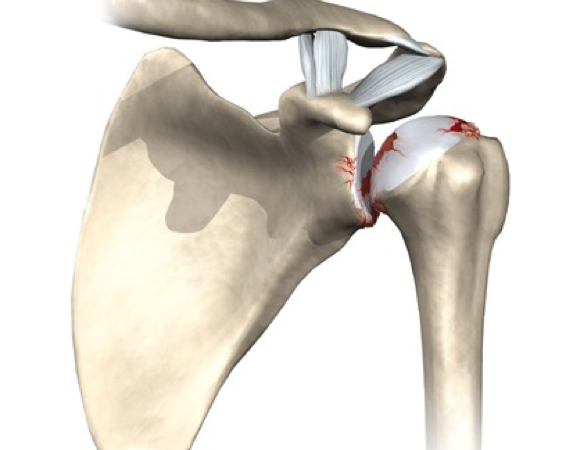

LESÃO DO MANGUITO ROTADOR

O manguito rotador é composto por 4 músculos: supraespinhal, infraespinhal, subescapular e redondo menor. A principal função desse grupo muscular e realizar os movimentos do ombro, bem como a estabilização da articulação. As lesões do manguito rotador constituem a ruptura total ou parcial desses tendões.. As causas da lesão podem ser degenerativas e traumáticas. No paciente idoso, com o processo de degeneração o tendão perde as suas propriedades fibroelásticas e torna-se susceptível ao surgimento dessas lesões. As causas traumáticas são observadas habitualmente em pacientes jovens, mas pode acometer os pacientes mais velhos também. Sintomas como dor no ombro e dificuldade para realizar a elevação do ombro e movimentos rotacionais são as queixas mais frequentes. O tratamento e individualizado para cada paciente. Mas as lesões com ruptura total ou lesões parciais com mais de 50% de extensão, associado a quadro de dor e dificuldade para realizar os movimentos do ombro, tendem a necessitar de cirurgia. Para lesões parciais com menos de 50% com quadro de dor pequeno e um bom movimento do ombro habitualmente indica-se a reabilitação com fisioterapia. A cirurgia utilizado é a artroscopia do ombro, podendo-se realizar a cirurgia aberta em raros casos. Após o procedimento utiliza-se uma tipoia durante cerca de 35 dias, onde após esse período o paciente iniciará a reabilitação fisioterápica.